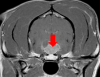

Cushing’s Disease

What is Cushing’s disease and how is steroid produced by the body? Hyperadrenocorticism or ‘Cushing’s disease’ is caused by excessive production or administration of steroid. It can be classified as pituitary dependent, adrenal dependent, or iatrogenic. A brief overview of how steroid is produced in the body will help with the understanding of this disease. […]